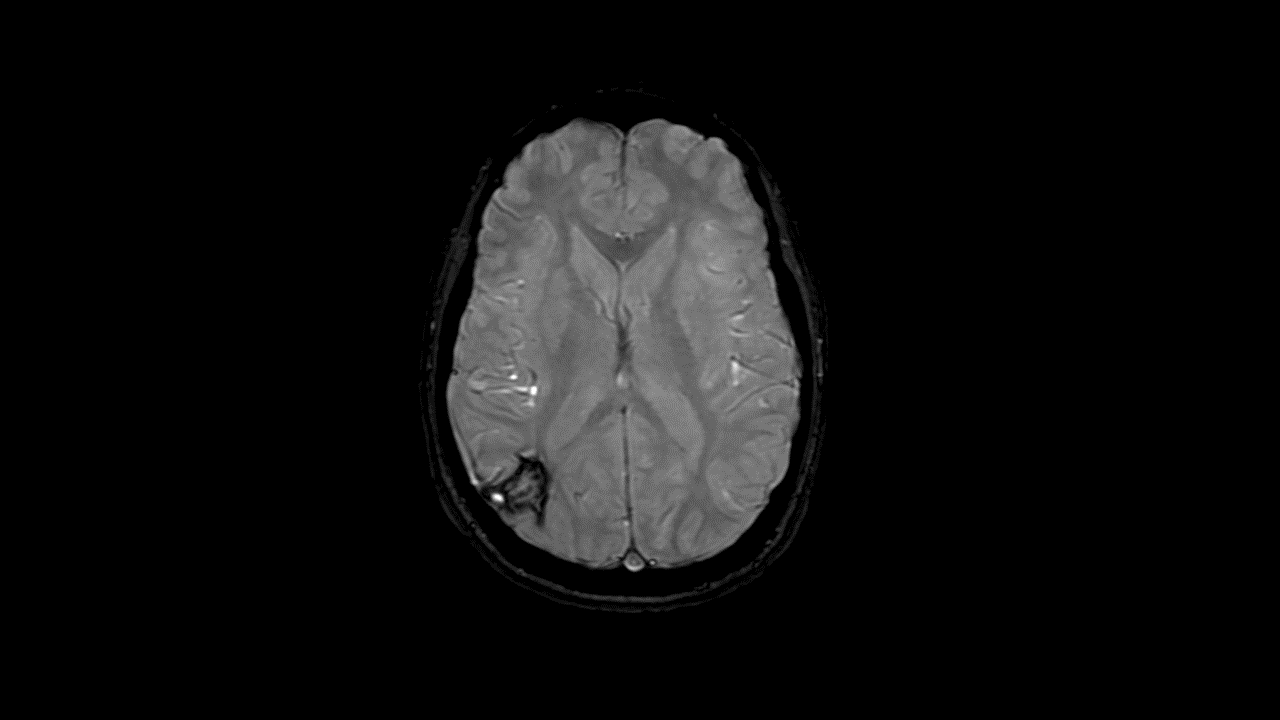

Clearly delineate small blood vessels, microbleeds, and large vascular structures in the brain.

SWAN helps delineate small blood vessels, microbleeds, and large vascular structures in the brain. It applies a multi-TE readout technique that generates more than double SNR and is inherently less affected by the chemical shift compared to conventional SWI techniques. Whole brain acquisition with 3D, sub-millimeter resolution takes ~4 minutes—image reconstruction is virtually instantaneous.